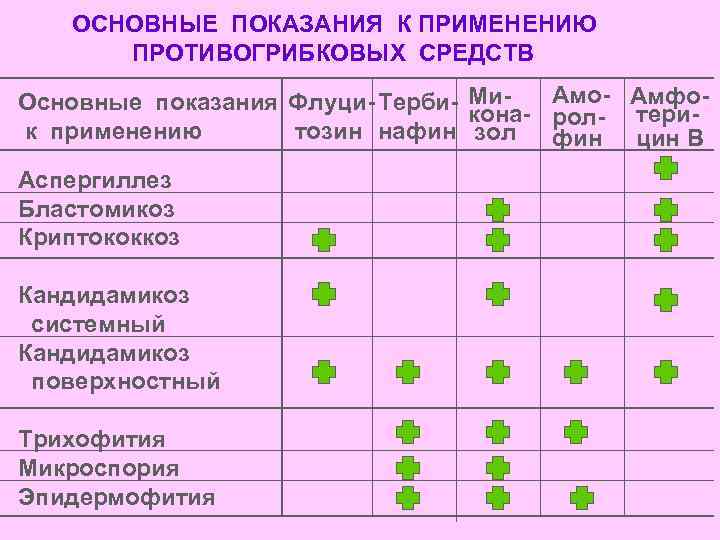

ОСНОВНЫЕ ПОКАЗАНИЯ К ПРИМЕНЕНИЮ ПРОТИВОГРИБКОВЫХ СРЕДСТВ Амо- Амфо. Основные показания Флуци- Терби- Микона- рол- терик применению тозин нафин зол фин цин В Аспергиллез Бластомикоз Криптококкоз Кандидамикоз системный Кандидамикоз поверхностный Трихофития Микроспория Эпидермофития